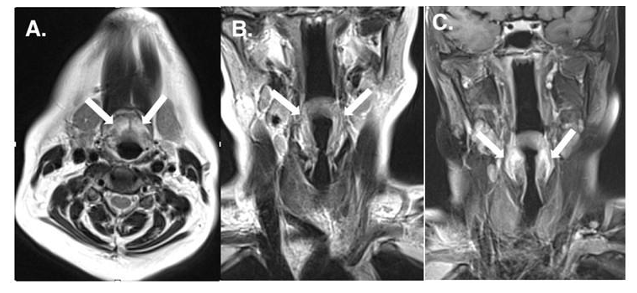

Late-onset Cerebrotendinous Xanthomatosis with Mild Symptoms: A Case Report

- Pei Shang, MD

- Case Report